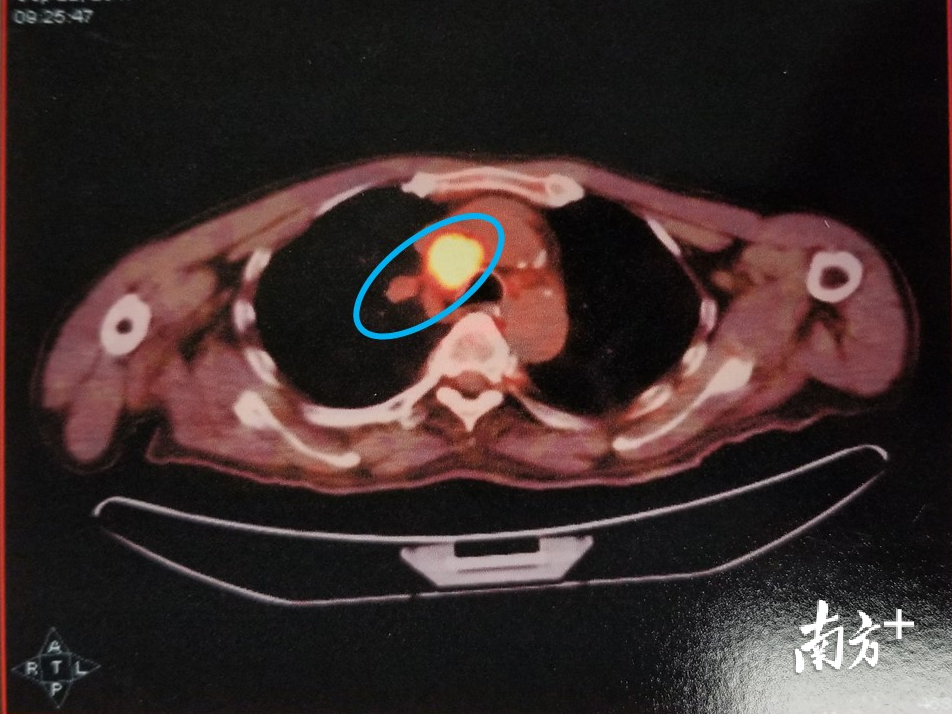

然而,史先生之前就诊过的两家医院都已经为史先生做过肺部CT的检查,影像报告并没有发现史先生的肺部有癌症。港大深圳医院神经内科医生们分析,有一种特殊的肺部肿瘤——“小细胞肺癌”,在癌症早期的CT检查中有可能漏诊,如果使用PET-CT检查则更容易发现。

家属接受了医生的建议,史先生完成了PET-CT检查。不出所料,PET-CT检查显示史先生的肺部和纵膈有一个很隐蔽,但生长非常旺盛的肿瘤样病变。